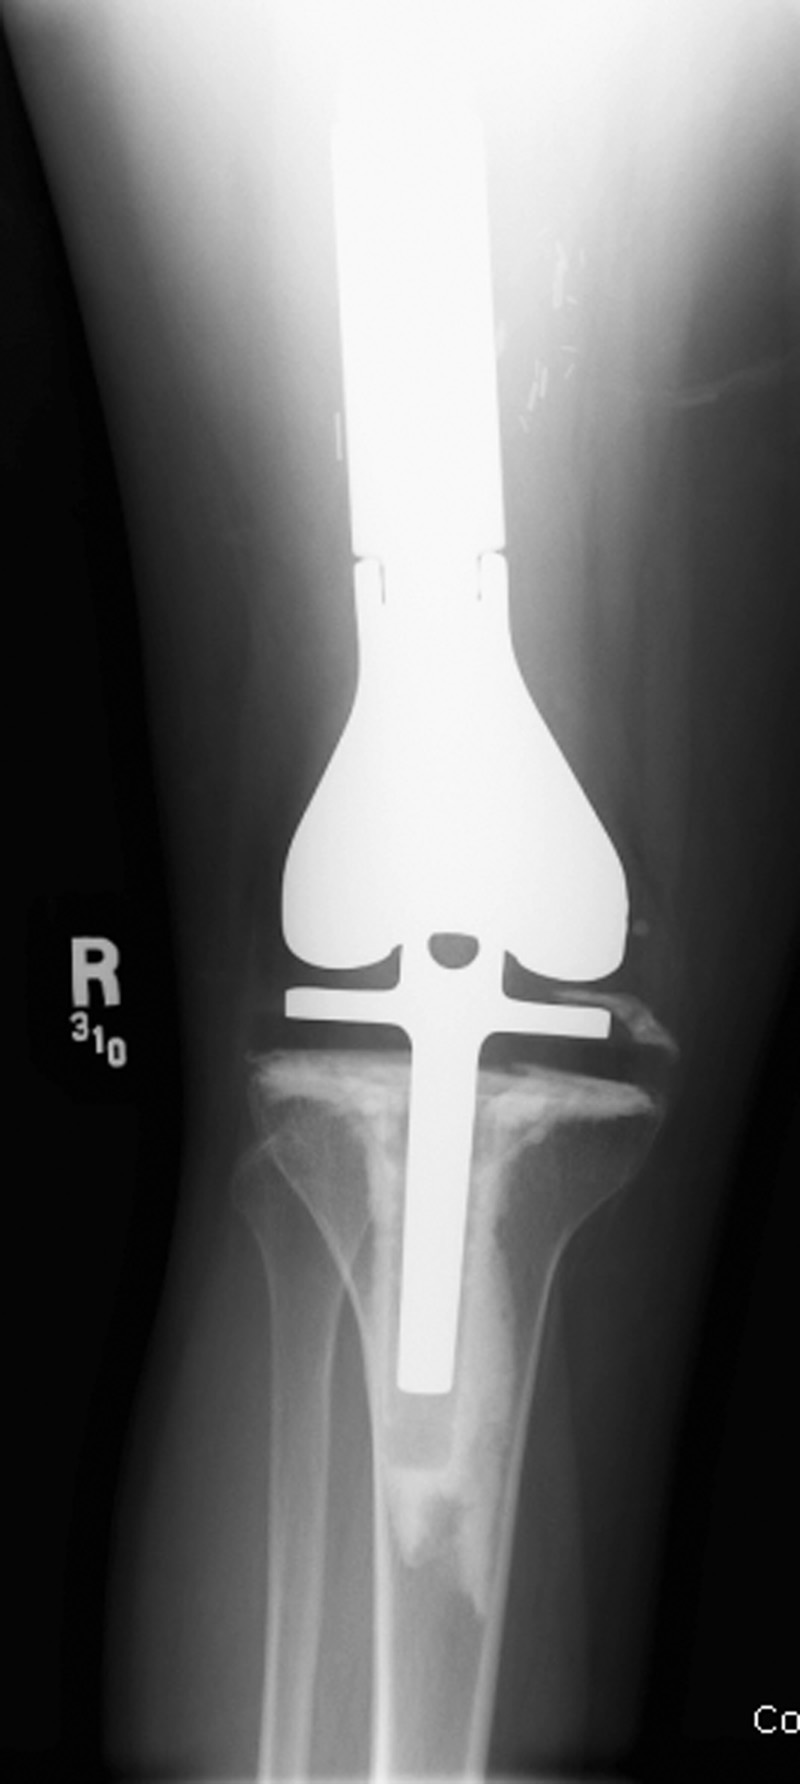

Rotating-hinge knee implant Rotating-hinge knee implant failure

Right knee revision arthroplasty Right knee revision implant Right knee revision implant failure Right knee revision implant failure

69 year-old man with revision of an infected right knee prosthesis (two left panels). A rotating-hinge knee implant was placed. Note the antibiotic beads about the medial aspect of the implant. The two fixation screws and wire are from prior surgery. There was implant failure with disruption of the implant six weeks later (two right panels).